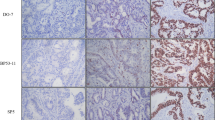

Immunohistochemical staining was carried out on TMAs using the PTEN monoclonal antibody 6H2.1 (Dako, Glostrup, Denmark) that has been used previously [34–36]. Essentially, tissue sections (3 μm) as TMAs were deparaffinised by heating the slides at 55-60°C for 2 hours, then soaking in xylene and hydrating by passing through a graded series of ethanol to water. Antigen retrieval was carried out by microwaving the slides in target retrieval solution pH 9 (DAKO). Endogenous peroxidase was quenched by incubating the slides in Peroxidazed I reagent (Biocare Medical, Concord, CA) for 5 min and background staining was blocked by incubation in Background Sniper reagent (Biocare Medical). Slides were stained using a 1:100 dilution of PTEN primary antibody 6H2.1 and detected using the MACH 3™ mouse HRP polymer detection system according to the manufacturer’s protocol (Biocare Medical). Slides were counterstained in methyl green (Sigma). The TMAs contained 3 sections taken from the same core. Each section was assessed by 2 blinded pathologists (JC and AR) and a majority score was determined for each pathologist (3 IHC readings). PTEN staining was mostly cytoplasmic. Intensity was scored on a four-tier system: 0, no staining; 1, weak; 2, moderate; and 3, strong. Loss of PTEN was defined as majority score 0 (Figure 2). The pathologist’s majority scores were compared directly for an IHC concordance rate. Specimens concordant on IHC were used for IHC versus TaqMan concordance rate.

The PTEN TaqMan® copy number assay (Hs03007912_cn, Life Technologies) was performed using 10 ng DNA in quadruplicate PCR. The primers provided in the assay were entirely within exon 9 of PTEN, at cytoband 10q23.31a, location Chr.10:89727445 on NCBI build 37 (Life Technologies). The assay is a duplex PCR for the PTEN gene and the reference gene, RNaseP (normaliser), set up according to the supplier’s protocol and run on the Rotorgene 6000 real time PCR instrument (Qiagen, Valencia, CA). The results are calculated as a ratio relative to a 2-copy control using the 2-∆∆Ct method (Rotorgene software), and multiplied by 2 to give the copy number. We tested DNA from colon cancer cell lines to determine the reproducibility of the assay and to select cell lines to use as copy number controls. HT29 (ATCC) is known to have 3 copies of chromosome 10 as determined by spectral karyotyping and comparative genomic hybridization [37] and was used as the primary control sample for 3 PTEN copies. Cell lines LIM2405, LIM1899 (both a kind gift from The Ludwig Institute, Melbourne) and HT29 were tested in quadruplicate and repeated in 3 separate PCR assays. The assay was both precise and reproducible - the means for LIM2405, LIM1899 and HT29 were 1.08 SEM 0.04, 2.07 SEM 0.03 and 2.96 SEM 0.07 respectively, and the coefficient of variation (CV) from run to run was 2.4%, and intra-assay CV was between 0.12% and 0.99%. These cell lines were therefore used as 1-, 2- and 3-copy controls respectively. Our group has previously described quantification of PTEN gene copy number on cell lines LIM2405 and LIM1899 [33]. For the patients’ DNA, loss of PTEN was defined as ≤1.5 copies, no loss was >1.5 copies.